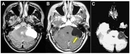

Rapor, sağ böbrek üst pole yerleşmiş bir lezyonu tanımlamaktadır. Bu lezyonun boyutları 35x30 mm olarak belirtilmiş ve düzgün konturlu olduğu ifade edilmiştir. Düzgün konturlu lezyonlar genellikle iyi huylu yapılarla ilişkilendirilir, ancak kesin bir değerlendirme için ek tetkiklere ihtiyaç vardır.

Lezyonun Özellikleri

Egzofitk yerleşim, lezyonun böbreğin dışına doğru büyüdüğünü göstermektedir. Bu durum, lezyonun doğasına dair ipuçları verebilir. Solit lezyonlar, genellikle tek başına bulunan ve çevresinde yayılım göstermeyen oluşumlardır. Ancak, bu tür lezyonların değerlendirilmesinde görüntüleme yöntemlerinin önemi büyüktür.

Rapor, kontrastlı tüm batın BT (Bilgisayarlı Tomografi) önerilmektedir. Bu tetkik, lezyonun özelliklerini daha ayrıntılı incelemek, çevresindeki dokularla olan ilişkisini değerlendirmek ve olası metastaz veya yayılım durumunu gözlemlemek açısından büyük önem taşımaktadır.